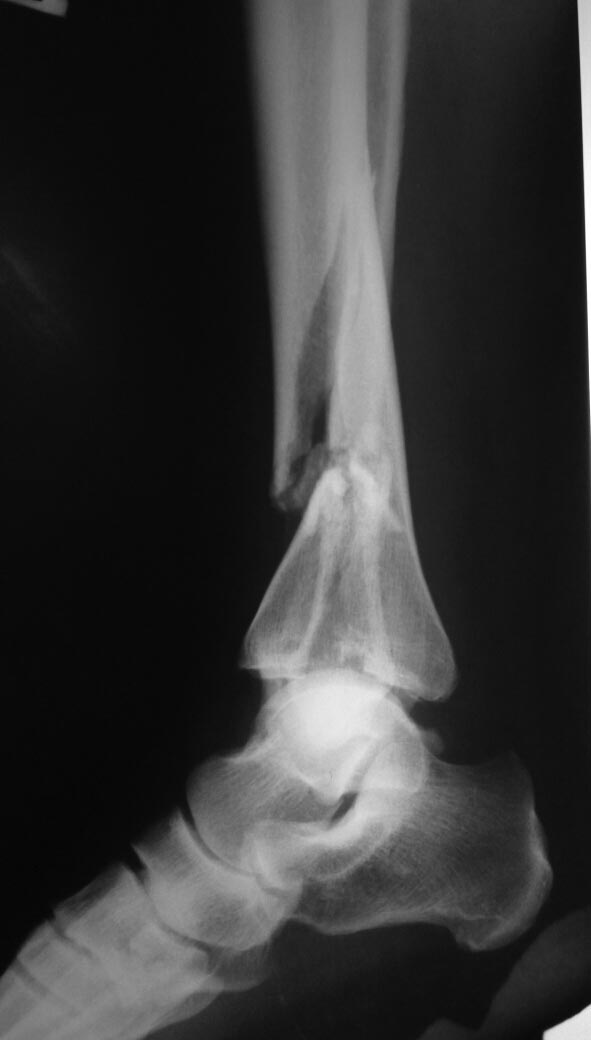

[Ortho] перелом типа "Пилон".

Пациентка 54 лет, упала со стула. Имеет место умеренный отек левой

голени, кожные покровы не пострадали. Склоняюсь к межотломковой

компрессии дистального фрагмента винтами и медиальной пластине с угловой

стабильностью. Второй вопрос об остеосинтезе малоберцовой

кости. Всем участникам спасибо.